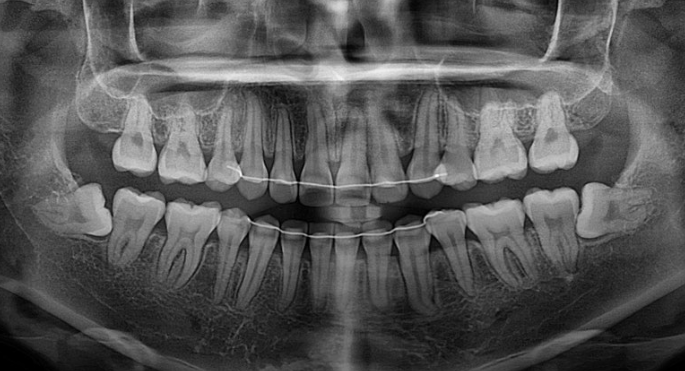

작은어금니 하나가 매복되었다시피 깊게 누워있습니다.

치료계획은 누워있는 덧니를 포함해서 작은어금니 4개 발치

치근흡수도 없고 치근평행도는 양호합니다.